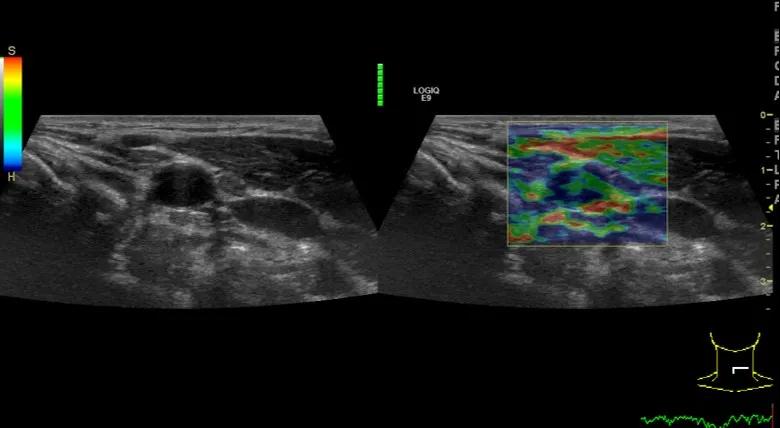

第四例是胸腺癌化妆包,术后、化疗之后淋巴结转移,肿块范围巨大,99mm*61mm,边界不清,呈浸润状,肿块包绕颈动脉,颈内静脉压闭,症状明显。由于患者放化疗也不敏感、血供非常丰富,于是采取多点姑息性消融。姑息性消融后未实现完全消融,病灶大片坏死,肿胀疼痛得到明显的缓解,后续患者未再来复查。

(病例4图例)